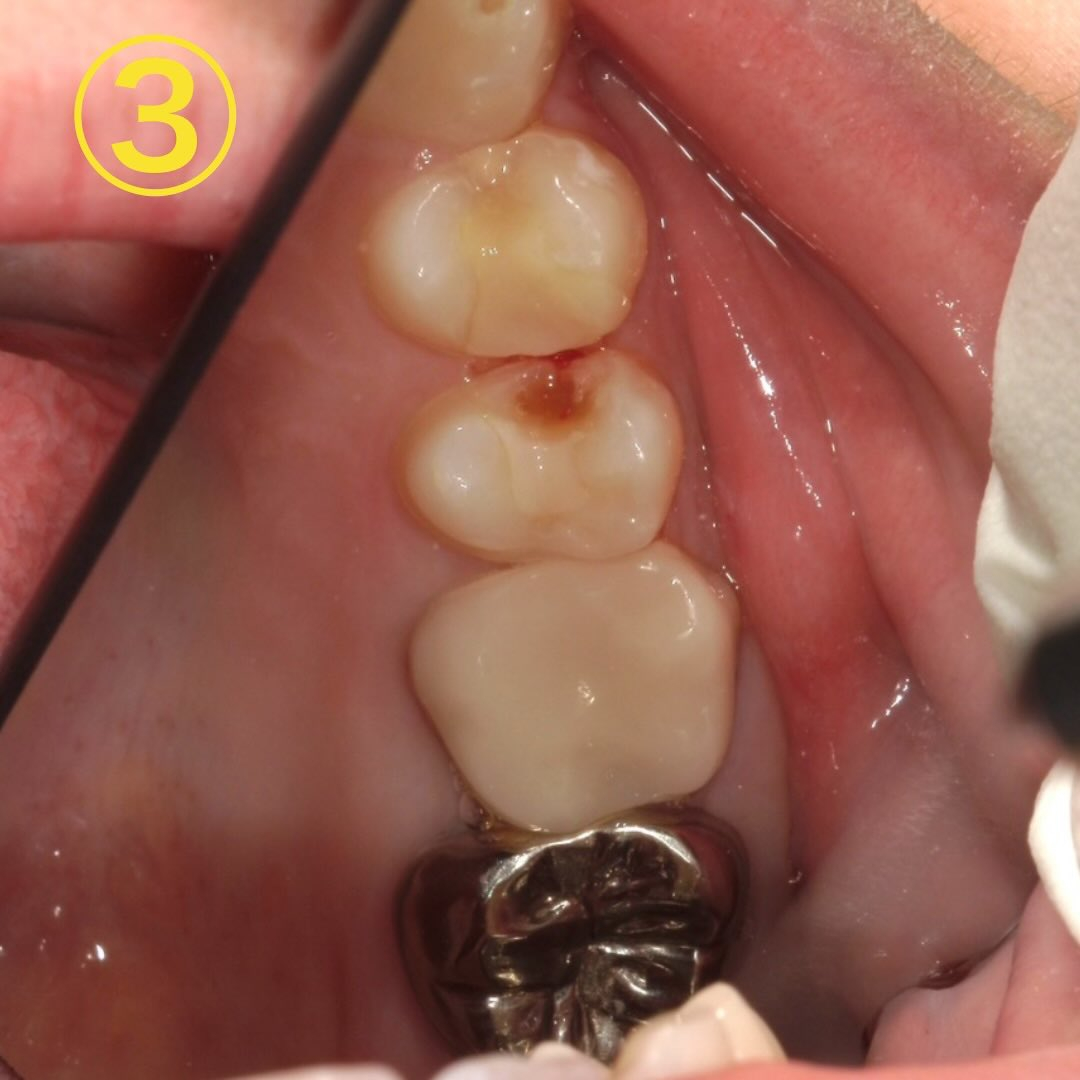

麻酔下で詰め物を取っていくと実際に虫歯がありました🧐→画像③

この虫歯が沁みる原因となっていたようです✍️